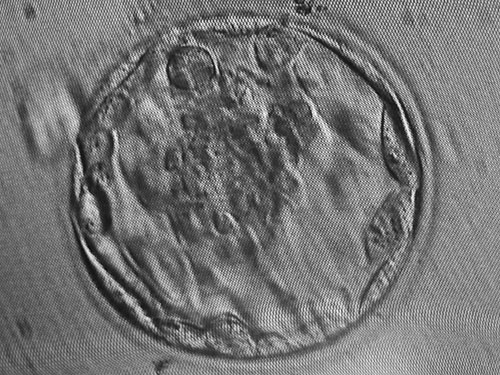

One of my embryos had reached blastocyst form, which is the ideal stage for embryos to be transferred, and that is why we had to wait for day-5 transfer rather than day-3.

Well, they are not “bad-bad”, but not what we were expecting. It turns out that alongside the blastocyst, I had one embryo at “morula” stage, which is not as good as blastocyst but it is the next best thing. The embryologist and the nurses recommended to transfer both of them to maximise the chance of pregnancy (basically, they didn’t want me to risk just going for the one embryo in case it failed). The problem with this? High risk of twins (see my previous post)